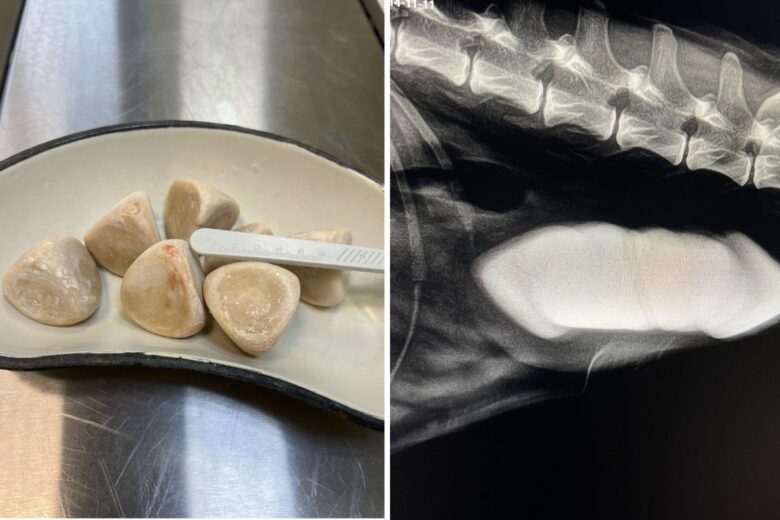

В Вологодской области ветеринары спасли собаку - для этого пришлось извлечь из ее мочевого пузыря гигантские камни общим весом более 350 граммов. Во время планового осмотра у десятилетней собаки по кличке Тора обнаружили семь камней размером до 5 сантиметров, которые угрожали жизни животного.

Специалисты областной станции по борьбе с болезнями животных провели сложную операцию и успешно удалили все конкременты. Сейчас питомица проходит восстановление и чувствует себя значительно лучше.